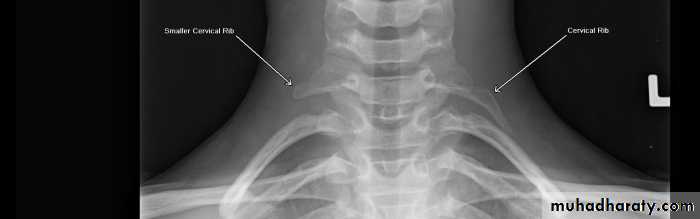

Chest and neck X-ray: may demonstrate

cervical ribs,

anomalous first ribs,

prominent transverse processes,

bony exostoses